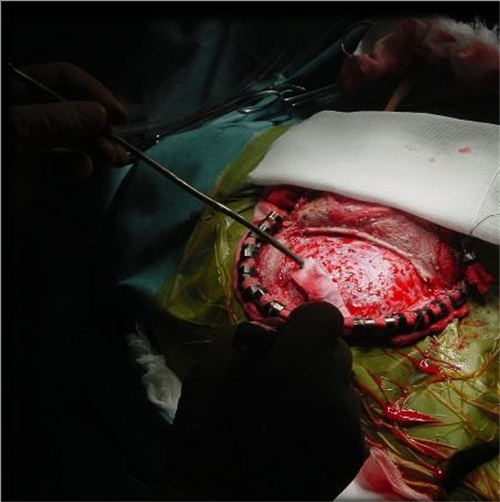

血管狹窄引起腦血管痙攣手術

手術治療煙霧病引起的腦血管痙攣

手術治療腦血管痙攣

手術治療腦血管痙攣的